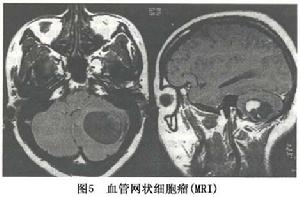

4.MRI 腫瘤T1像信號高於腦脊液為等T1;T2像為長T2信號,並可見腫瘤周圍水腫帶或小的血管流空影。此病應注意與小兒常見的後顱凹囊性星形細胞瘤鑑別。

MRI可見血管網狀細胞瘤T1像的信號強度高於腦脊液T2像為長T2改變。瘤結節多為等T1長T2像病灶輪廓顯示上優於CT,T2像上見到腫瘤周圍長T2的水腫帶。